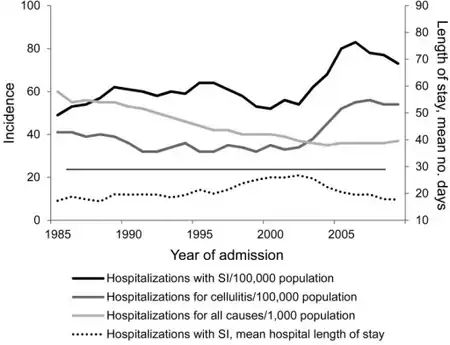

Staphylococcus bacteria is one of the leading community-acquired bacteria. According to the CDC, after a push from hospitals to better prevent staph infections, the percentage of people affected has dropped dramatically. However, staph infections are still prominent and a cause for concern among healthcare professionals, especially new antibiotic-resistant strains. [36][37][38]

In the United States, in 2017 some 119,000 people suffered from bloodstream Staphylococcus aureus[18] whereas other industrialized countries have an average incidence rate of 10 to 30 per 100,000 person-years.[36]

- ↑ Gutierrez, Kathleen; Halpern, Meira S.; Sarnquist, Clea; Soni, Shila; Arroyo, Anna Chen; Maldonado, Yvonne (January 2013). "Staphylococcal infections in children, California, USA, 1985-2009". Emerging Infectious Diseases. 19 (1): 10–20, quiz 185. doi:10.3201/eid1901.111740. ISSN 1080-6059. Retrieved 28 December 2022.